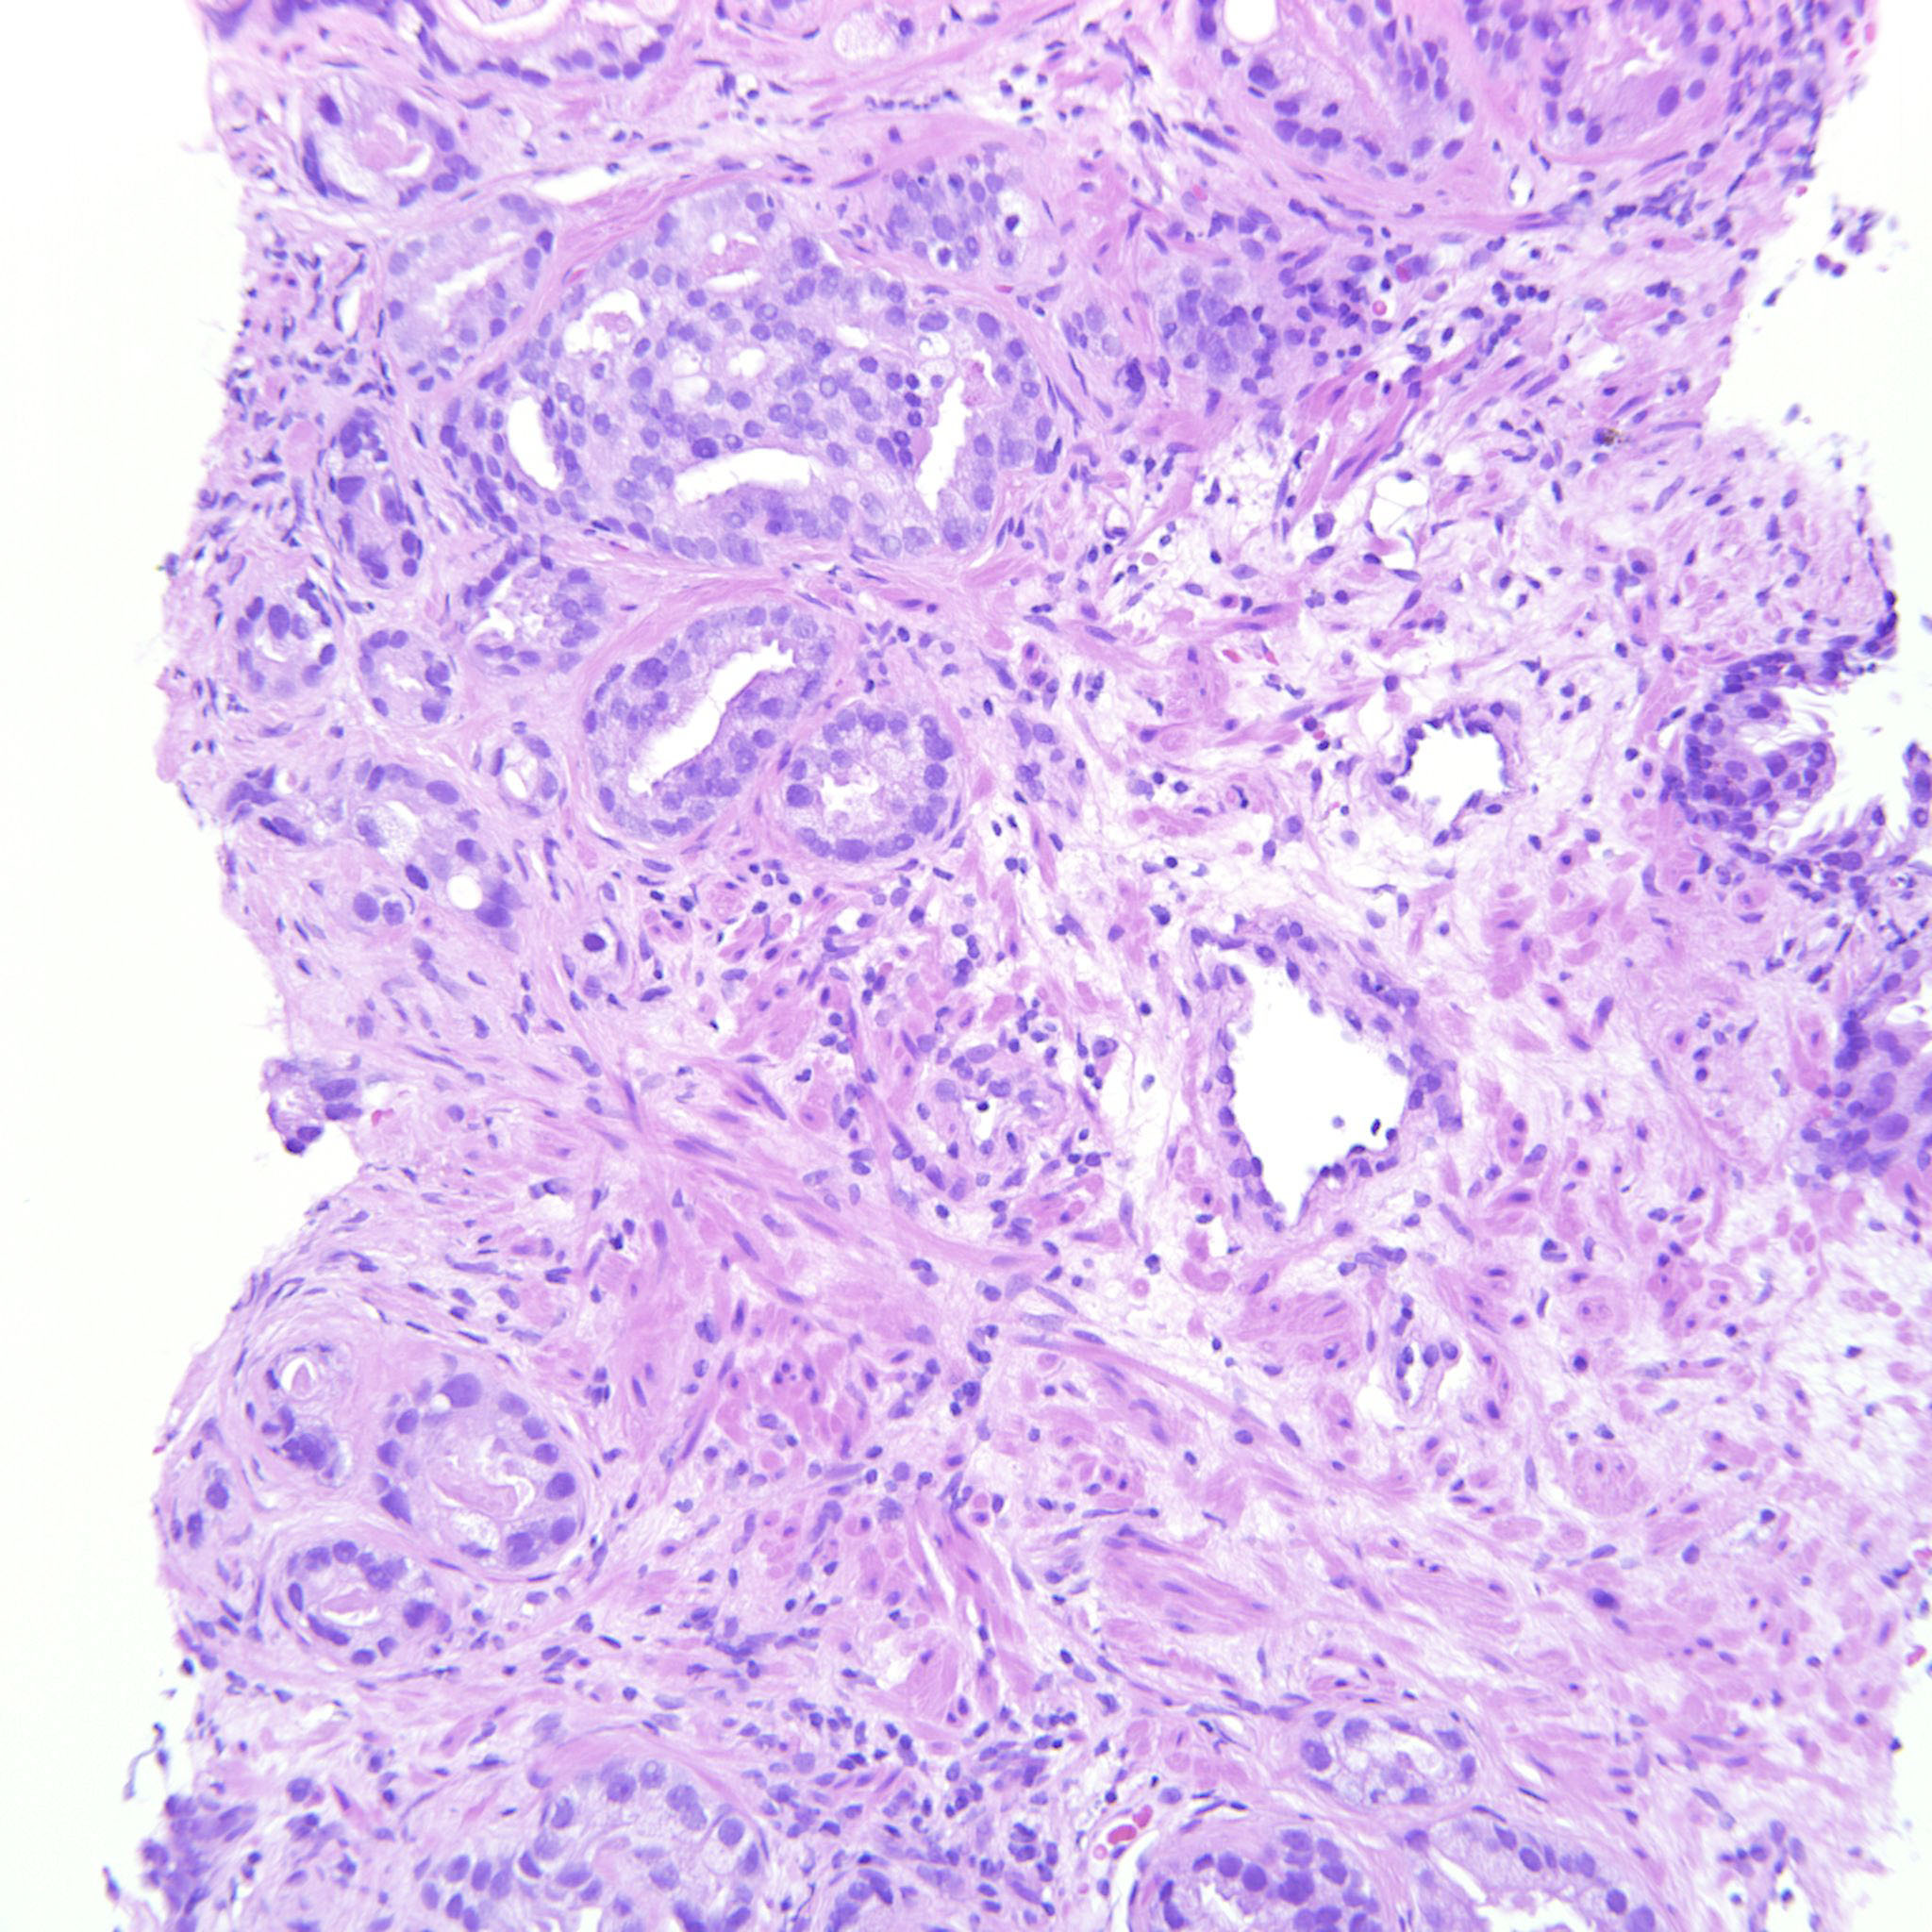

Prostate cancer grading

Case ID: 146